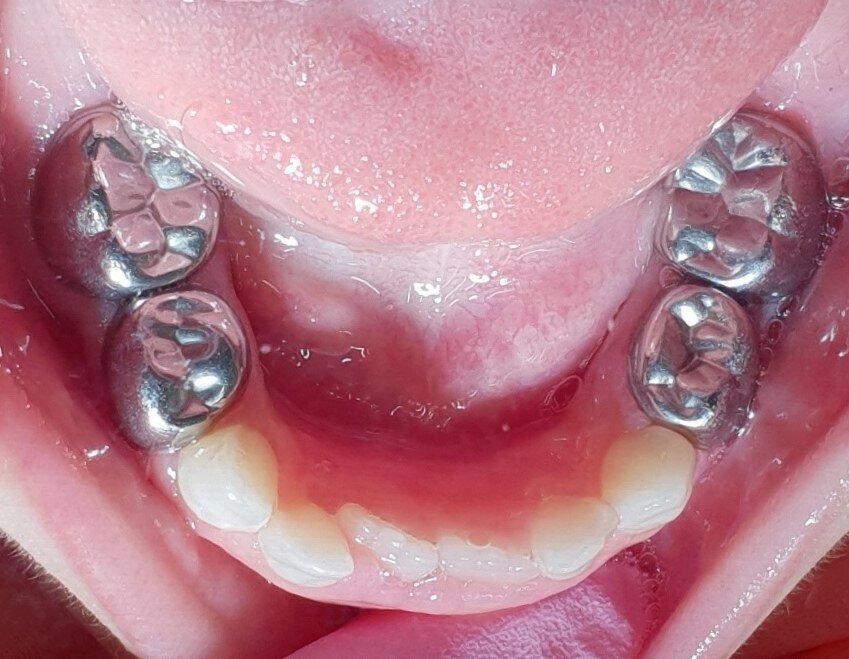

Afbeelding 1: Laat de ouders bij de mondinspectie en behandelplanning op de stoel van de assistent zitten en betrek hen bij het zorgplan.

Afbeelding 2: Laat de ouders bij de mondinspectie en behandelplanning op de stoel van de assistent zitten en betrek hen bij het zorgplan.